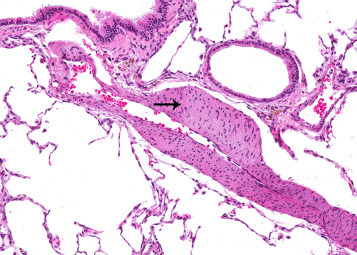

The pulmonary trunk gives rise to right and left pulmonary arteries. Each lobe has one single axial artery from which the branches arise (Hislop and Reid, 1978). Two types of arteries branch from the axial artery to supply each lobe. One type arises at an acute angle and the second type branches at a right angle from the axial artery (Lane et al., 1983). Morphologically, the two types of vessels differ with respect to their muscular layers. At the hilum of the lung the tunica media of the pulmonary artery consists of a circumferentially arranged layer of smooth muscle bounded by internal and external elastic laminae. Some arteries have an oblique muscle layer external to the external elastic lamina and the circular muscular layer. The oblique muscle layer makes the vessel wall appear unusually thick relative to the diameter of the lumen and has been mistaken for medial hypertrophy. As these arteries decrease in size, the circular muscle layer ends, but the oblique muscle layer continues as a discrete spiral bundle (Figure 23.5 ). On cross-section, the vessel may appear to have an irregularly thickened muscle. Eventually the arterial branches become nonmuscular, usually at the level of the alveolar duct. The function of this oblique muscle segment is not known (Meyrick et al., 1978).

Figure 23.5.

External oblique muscle (arrow) surrounding a right-angle branch artery. This is a unique feature of the rat pulmonary vasculature.